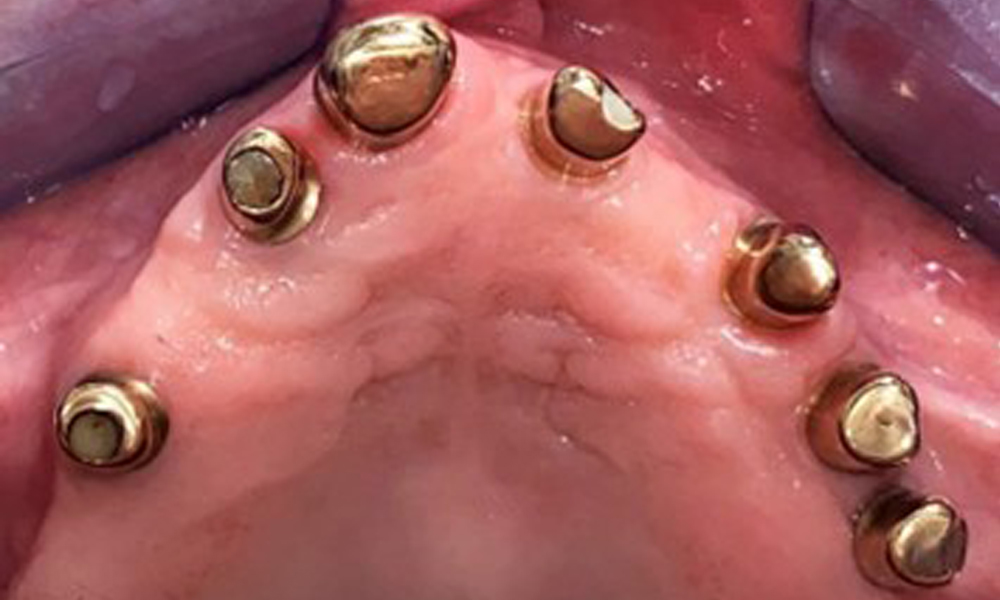

The dental findings are as follows: Combined removable implant and tooth-supported telescopic prostheses on implants 15, 13, 21, 23, 24, 25 and tooth 11 (Fig. 1, Fig. 2, Fig. 3). The patient was fitted with a fixed mandibular denture. Adequate bridges were present over 37 to 34 and 45 to 47 (Fig. 4), the crown margins were intact and there were no active caries. A composite filling with a marginal gap was present on tooth 43. There was mandibular gingival recession, exposing 1 to 3 mm of root surface. This also applies to 11.

Occlusal view: Maxilla with tooth and implant-supported telescopic prostheses.

Fig. 2: Occlusal view: Maxilla with tooth and implant-supported telescopic prostheses

Occlusal view: Maxilla with removable, palateless denture.

Fig. 3: Occlusal view: Maxilla with removable, palateless denture.